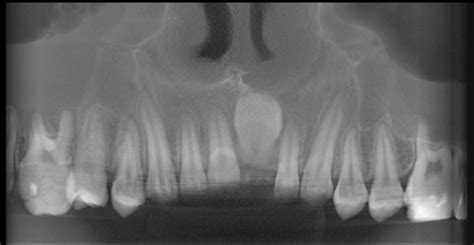

A continuación, se presenta un caso clínico de una paciente de nueve años con un incisivo central superior derecho impactado, tratado mediante un enfoque ortodóncico-quirúrgico.

- Examen radiográfico: incisivo central superior derecho cerca de la espina nasal anterior, situado perpendicularmente al plano oclusal.

- Fase I: Alineación y nivelación. Consolidación de espacio para posterior tracción del OD 11.

- Fase II: Fase quirúrgica de exposición, colocación de botón y ligado para tracción del OD 11. Arco acero 0.016” x 0.022”.

- Fase III: Tracción e incorporación del incisivo central derecho a la arcada. Retiro de botón, colocación de bracket en OD 11.

- Radiográficamente un buen paralelismo radicular.